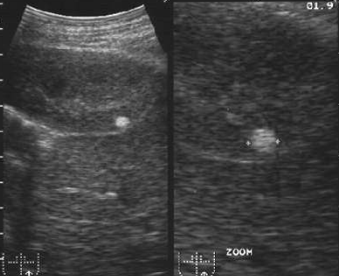

| Рис. 6.23. Сонограмма левой почки. Определяется объемное гипоэхогенное образование (стрелка) с неровными контурами в области верхнего полюса левой почки. Почечно-клеточный рак левой почки. |

| Рис. 6.24. Сонограмма левой почки. В области паренхимы левой почки определяется повышенной эхогенности образование с четкими контурами (стрелки). Ангиомиолипома (доброкачественная опухоль) левой почки. |